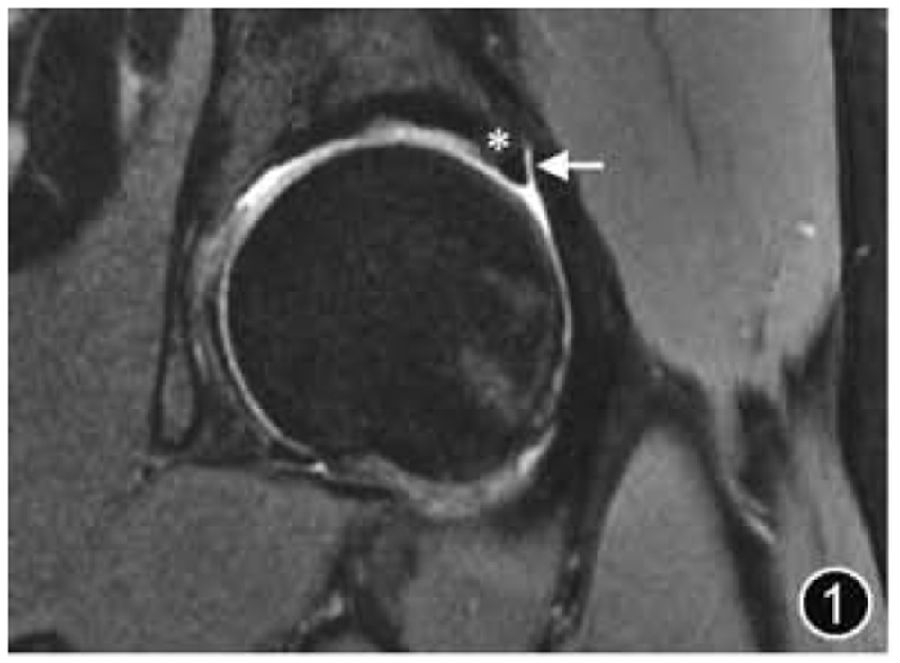

2.髋臼盂唇损伤:髋臼盂唇损伤可能由外伤导致,也可能因关节活动及过度运动而发生退变、磨损和撕裂,DDH、FAI及其他髋关节形态异常易导致盂唇损伤。大多数髋臼盂唇撕裂发生在髋关节的前部或前上区,孤立的盂唇后部撕裂不常见。髋臼盂唇撕裂的位置应使用Blankenbaker 钟面来描述,或者使用传统的解剖描述,如前、前上等。盂唇撕裂可分为部分撕裂和骨盂唇交界处撕裂,两种类型可同时发生。如果盂唇内见局限性高信号,则诊断为盂唇损伤,应报告盂唇形态改变(变薄、增生)、盂唇损伤的性质(退变、磨损)及程度(轻度、中度或重度)。如果观察到自盂唇关节侧穿过盂唇基底部或进入盂唇实质内的线样高信号,则认为存在撕裂(图3),应提及撕裂的位置、分型、长度及是否存在盂唇分离。如果伴有盂唇内或盂唇旁囊肿,应描述大小和位置。

图3 髋臼盂唇撕裂MRI图像。冠状面T2WI示髋臼外上盂唇撕裂(短↑)伴盂旁囊肿形成(长↑)